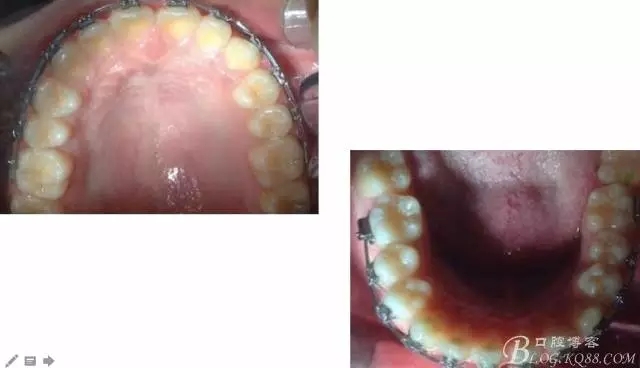

一晃快兩年了,我覺得關節(jié)重建及咬合穩(wěn)定,再加上患者的急迫愿望,我們拆除了矯正器。

尖牙關系中性,磨牙關系中性,咬合鎖結(jié)良好!

15歲了,1米78的個頭,陽光帥氣的他,側(cè)貌堪比天安門國旗手的面型?。釘懒耍?/p>